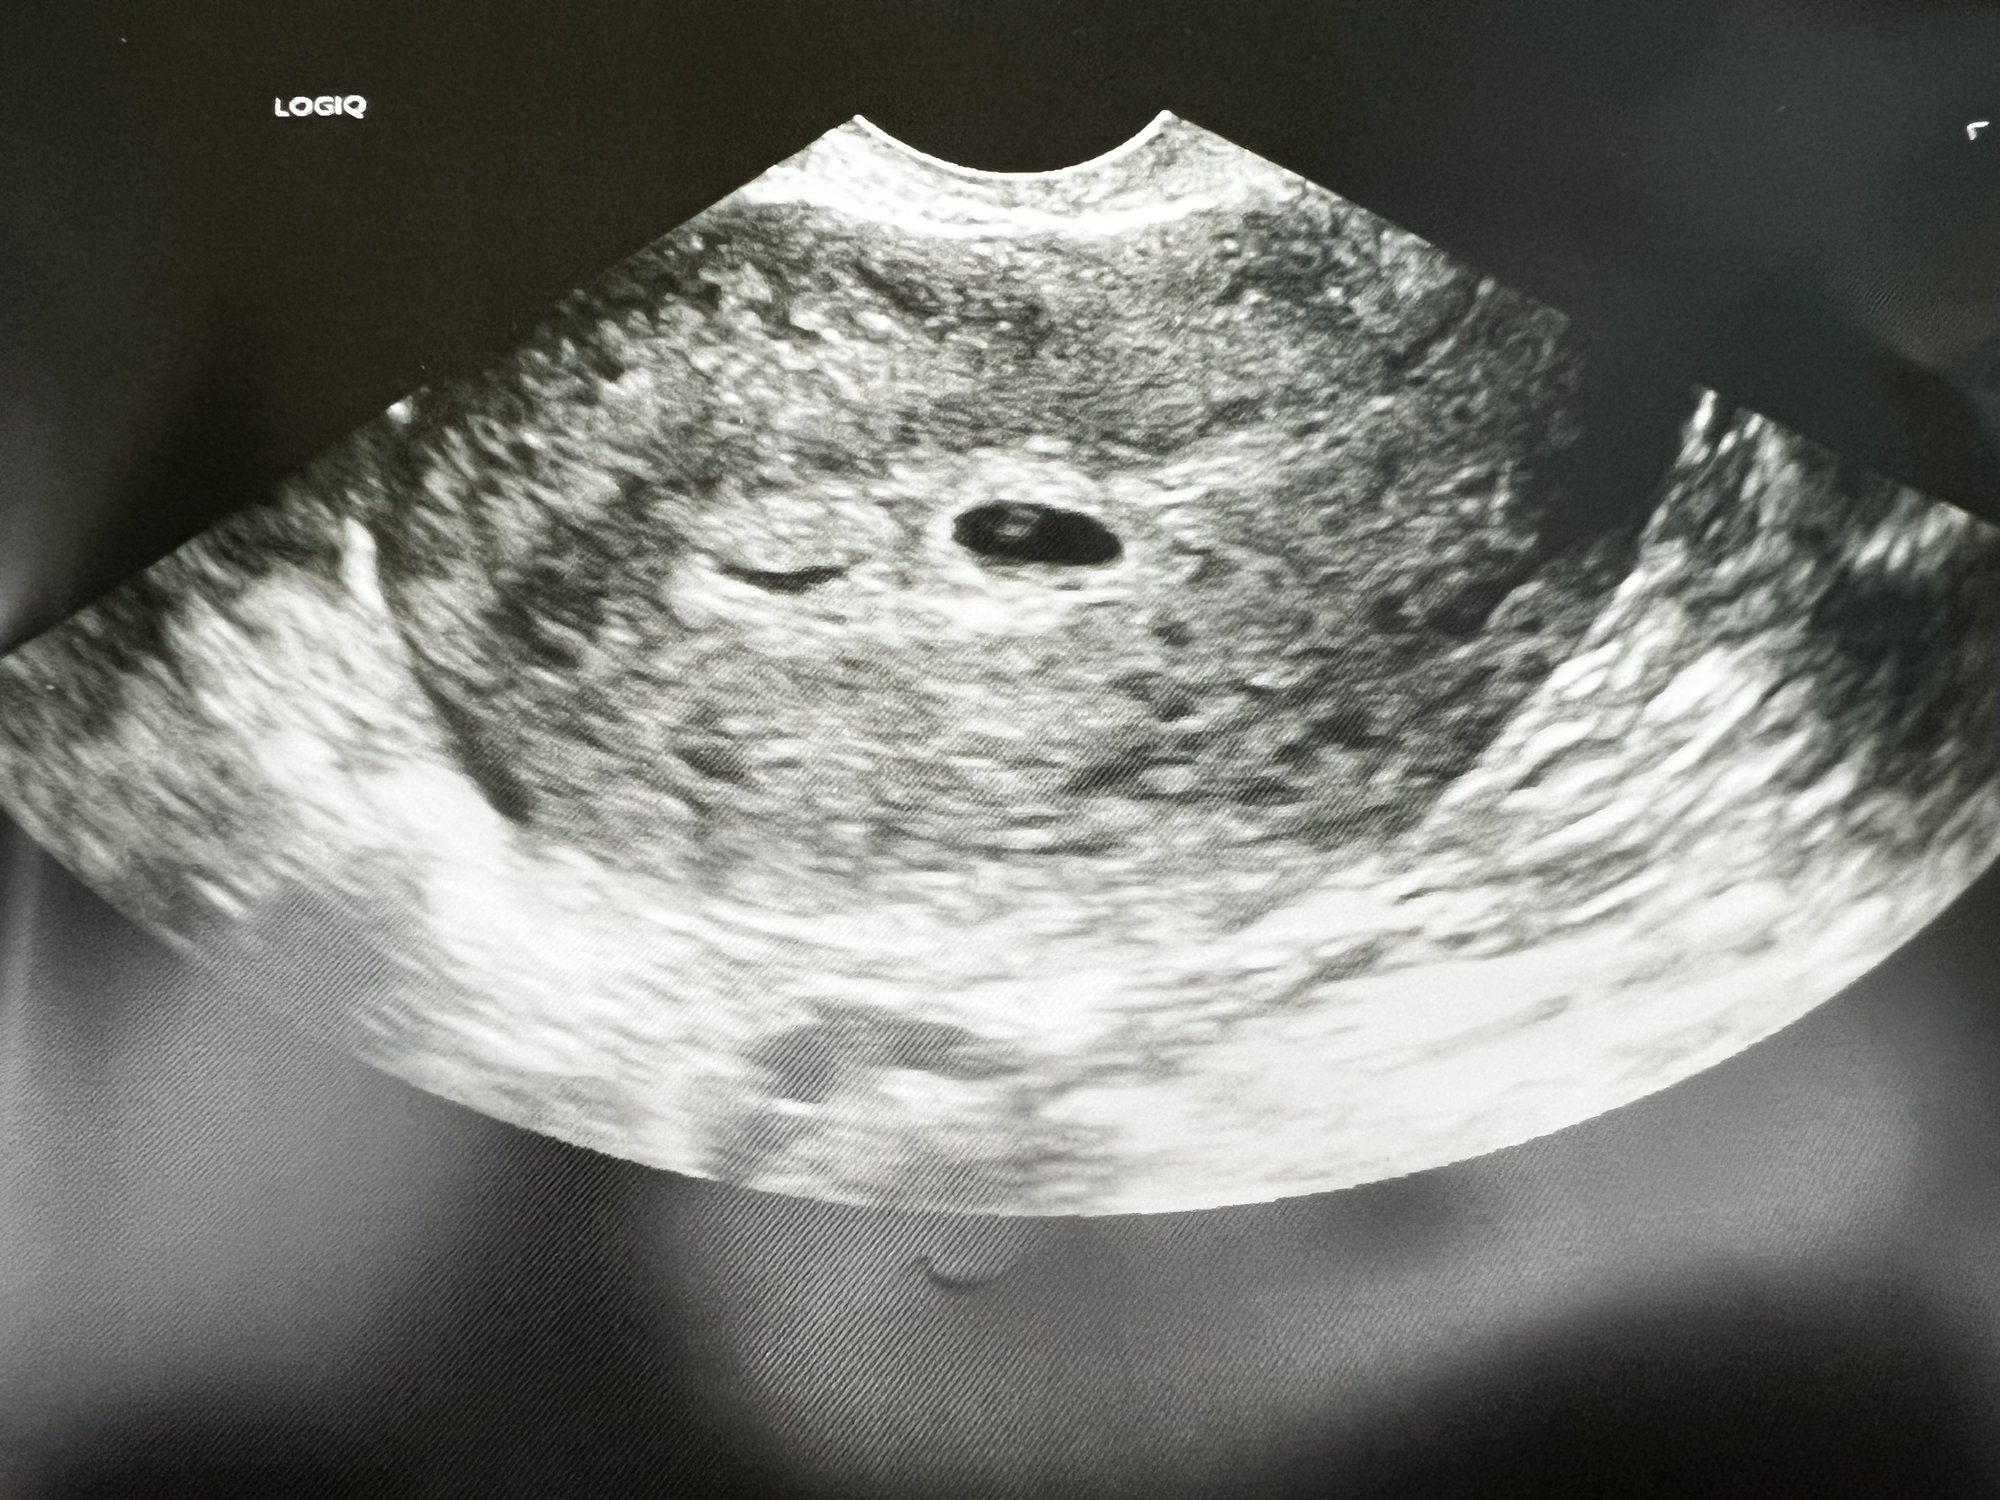

Had my first US at 5w2d as my obgyn was suspecting an ectopic pregnancy due my history of loss. Saw a gestational sac and yolk sac no fetal pole tough! I have my next US up at week 7. So nervous!